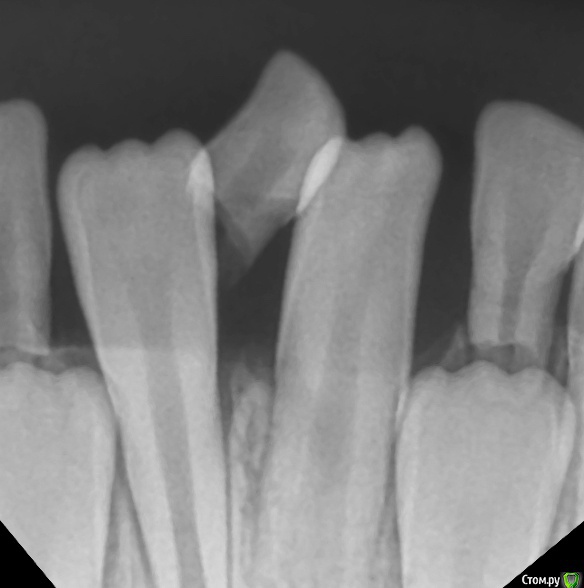

CRAZYDUCK Опубликовано 14 февраля, 2020 Автор Поделиться Опубликовано 14 февраля, 2020 Красивое красное фото ! Резорбция корня временного Резца почти полная , но уходить он не хочет . Удалила и жлеммна осмотр через месяц . Ссылка на комментарий